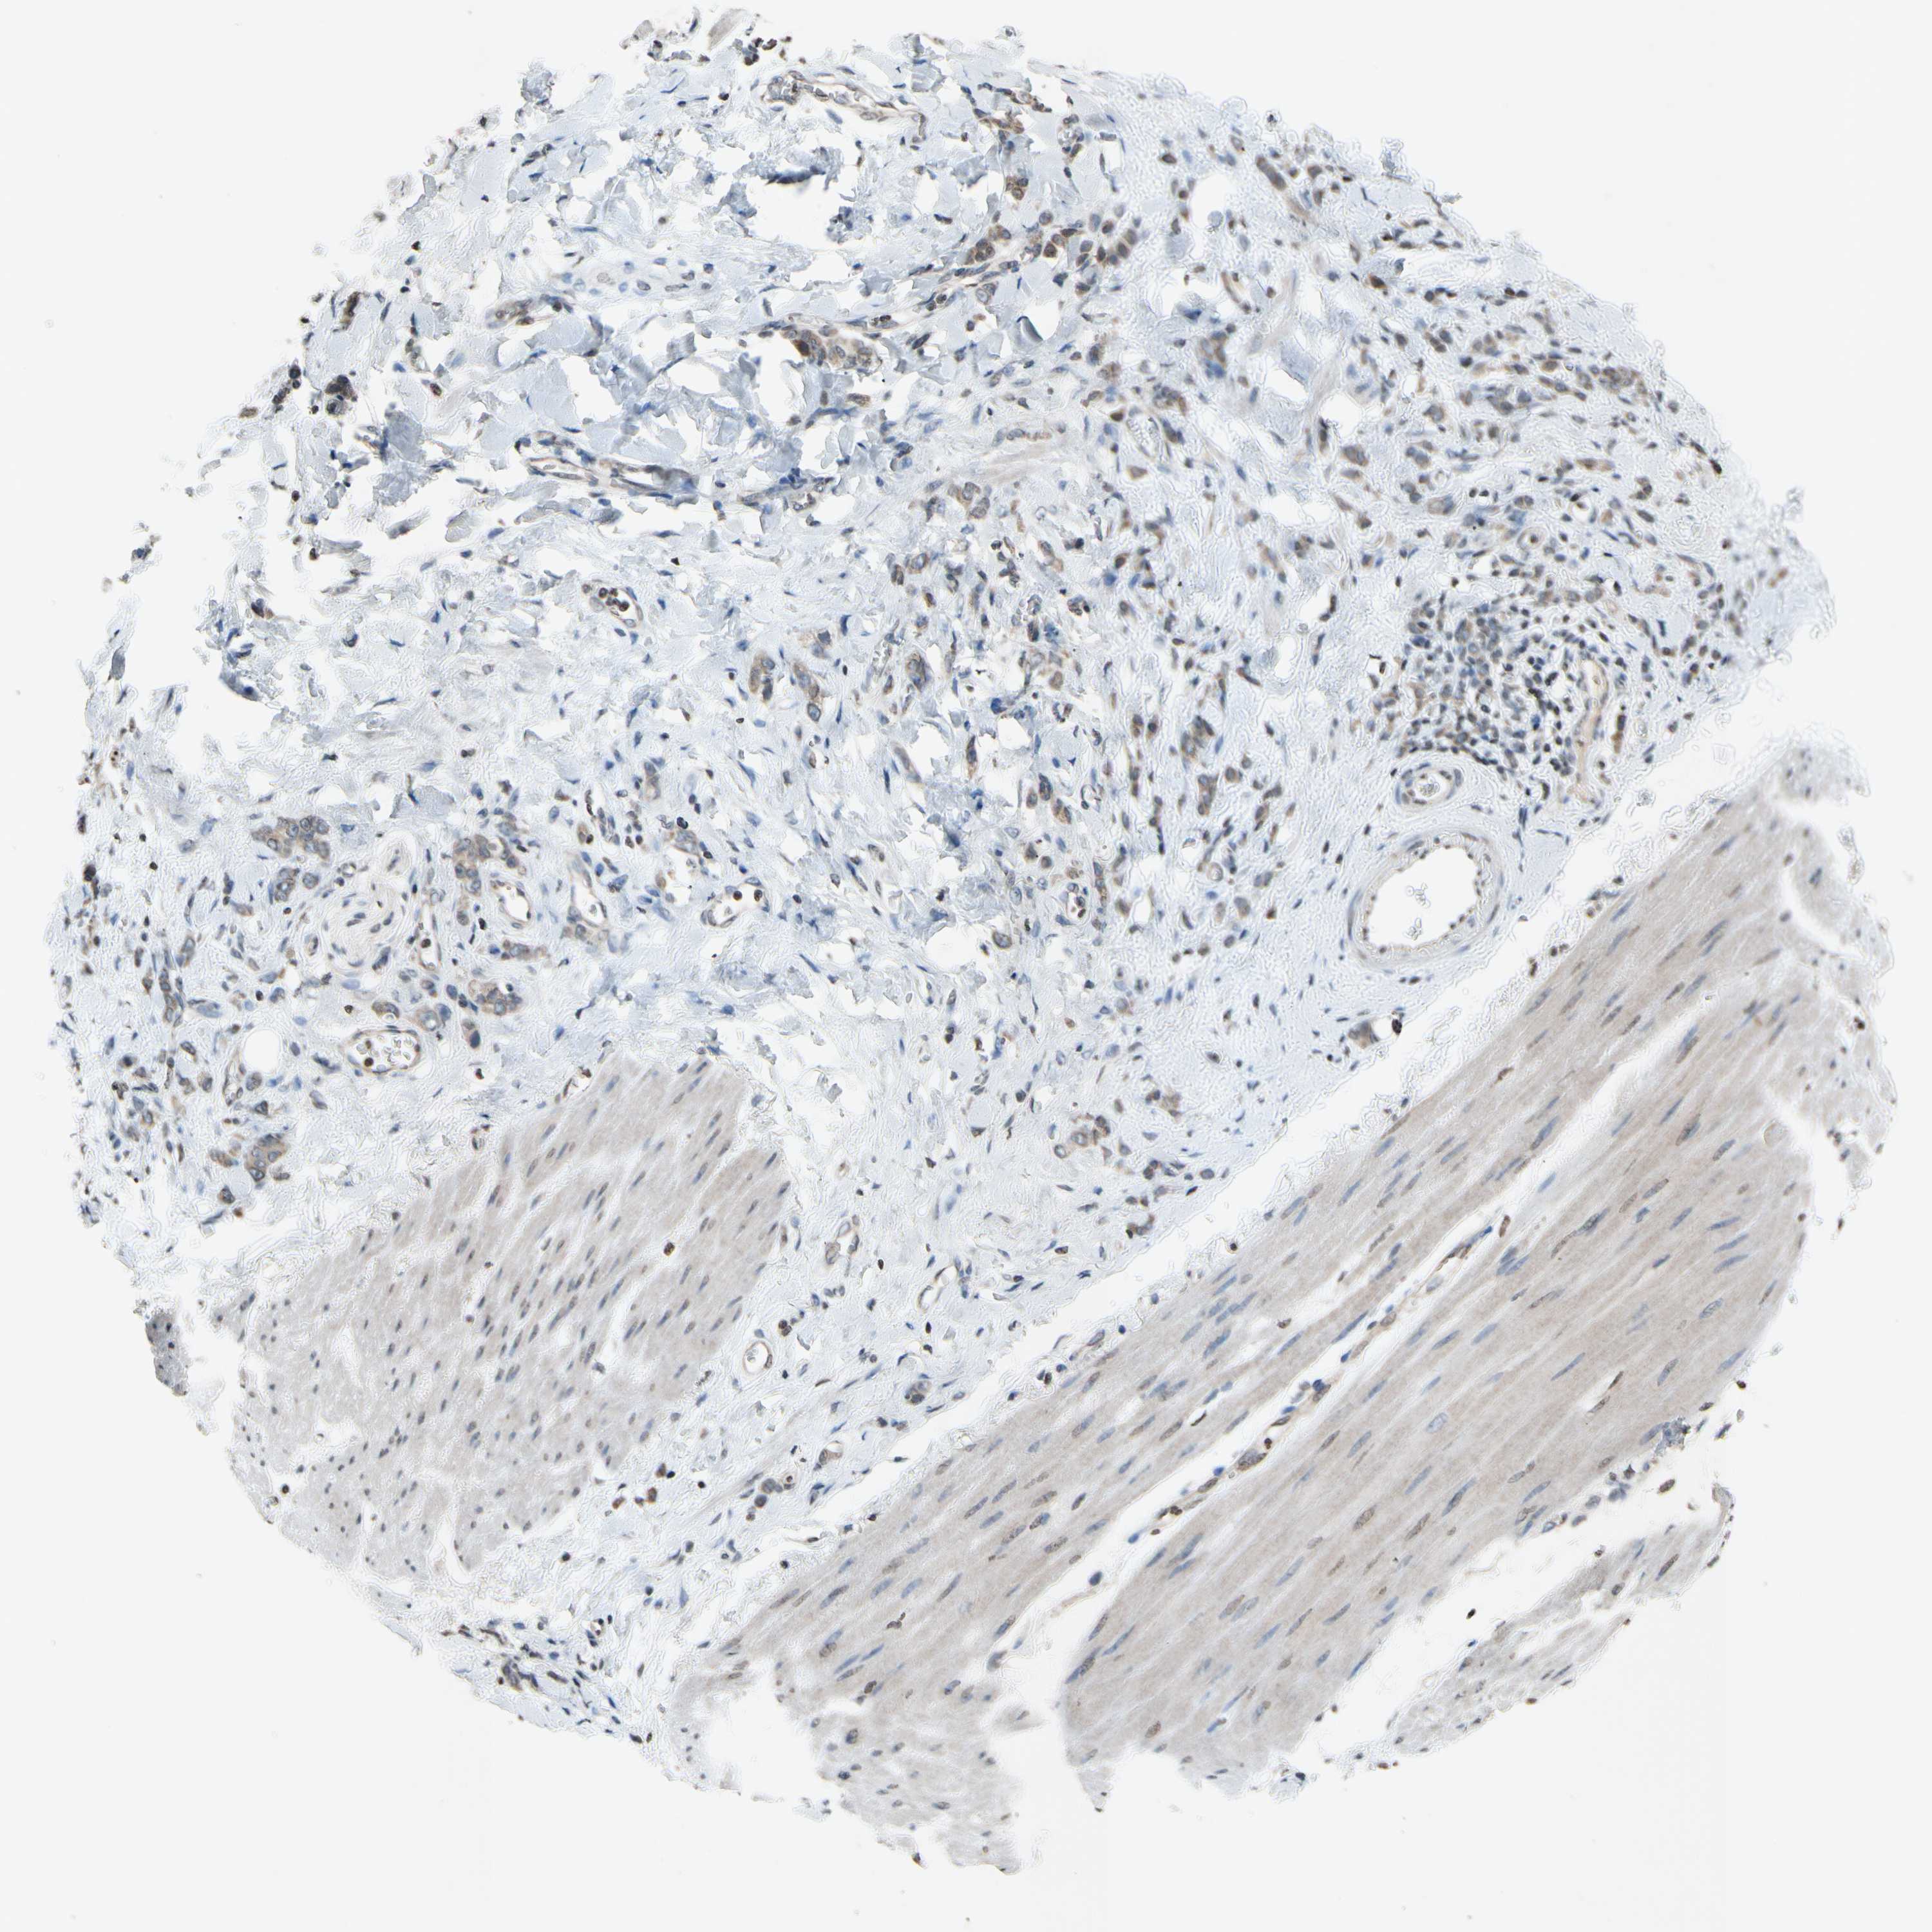

STOMACH CANCER - Protein expressioni

A mouse-over function shows sample information and annotation data. Click on an image to view it in a full screen mode. Samples can be filtered based on level of antibody staining by selecting one or several of the following categories: high, medium, low and not detected. The assay and annotation is described here.

Note that samples used for immunohistochemistry by the Human Protein Atlas do not correspond to samples in the TCGA dataset.

Antibody stainingi

Antibody staining in the annotated cell types in the current human tissue is reported as not detected, low, medium, or high, based on conventional immunohistochemistry profiling in selected tissues. This score is based on the combination of the staining intensity and fraction of stained cells.

Each image is clickable and will lead to virtual microscopy that enables deeper exploration of all samples and also displays staining intensity scores, fraction scores and subcellular localization as well as patient and tissue information for each sample.

Antibody HPA013166

Antibody CAB009789

Staining

High

Medium

Low

Not detected

Intensity

Strong

Moderate

Weak

Negative

Quantity

>75%

75%-25%

<25%

None

Location

Nuclear

Cytoplasmic/membranous

Cytoplasmic/membranous,nuclear

Adenocarcinoma, NOS

Adenocarcinoma, High grade